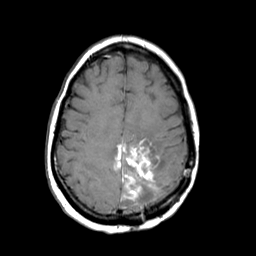

MR Study #3 -- Slice #37

Tour 1: Next/Previous/Start: The core of this lesion contains elements which enhance with gadolinium, as seen here at the same slice location as before. Choose a spatial movie of this data (by choosing "cine" next to the sagittal image), to see the entire extent of gadolinium enhancement. Note that there is extension of the enhancing portion of the mass to the right hemisphere. In this T1-weighted series, highest signal comes from water which has had its relaxation time shortened because of proximity to molecules of the injected contrast agent gadolinium-DTPA. Such signal is generally seen from water which is either intravascular or within regions of breakdown of the blood-brain barrier.